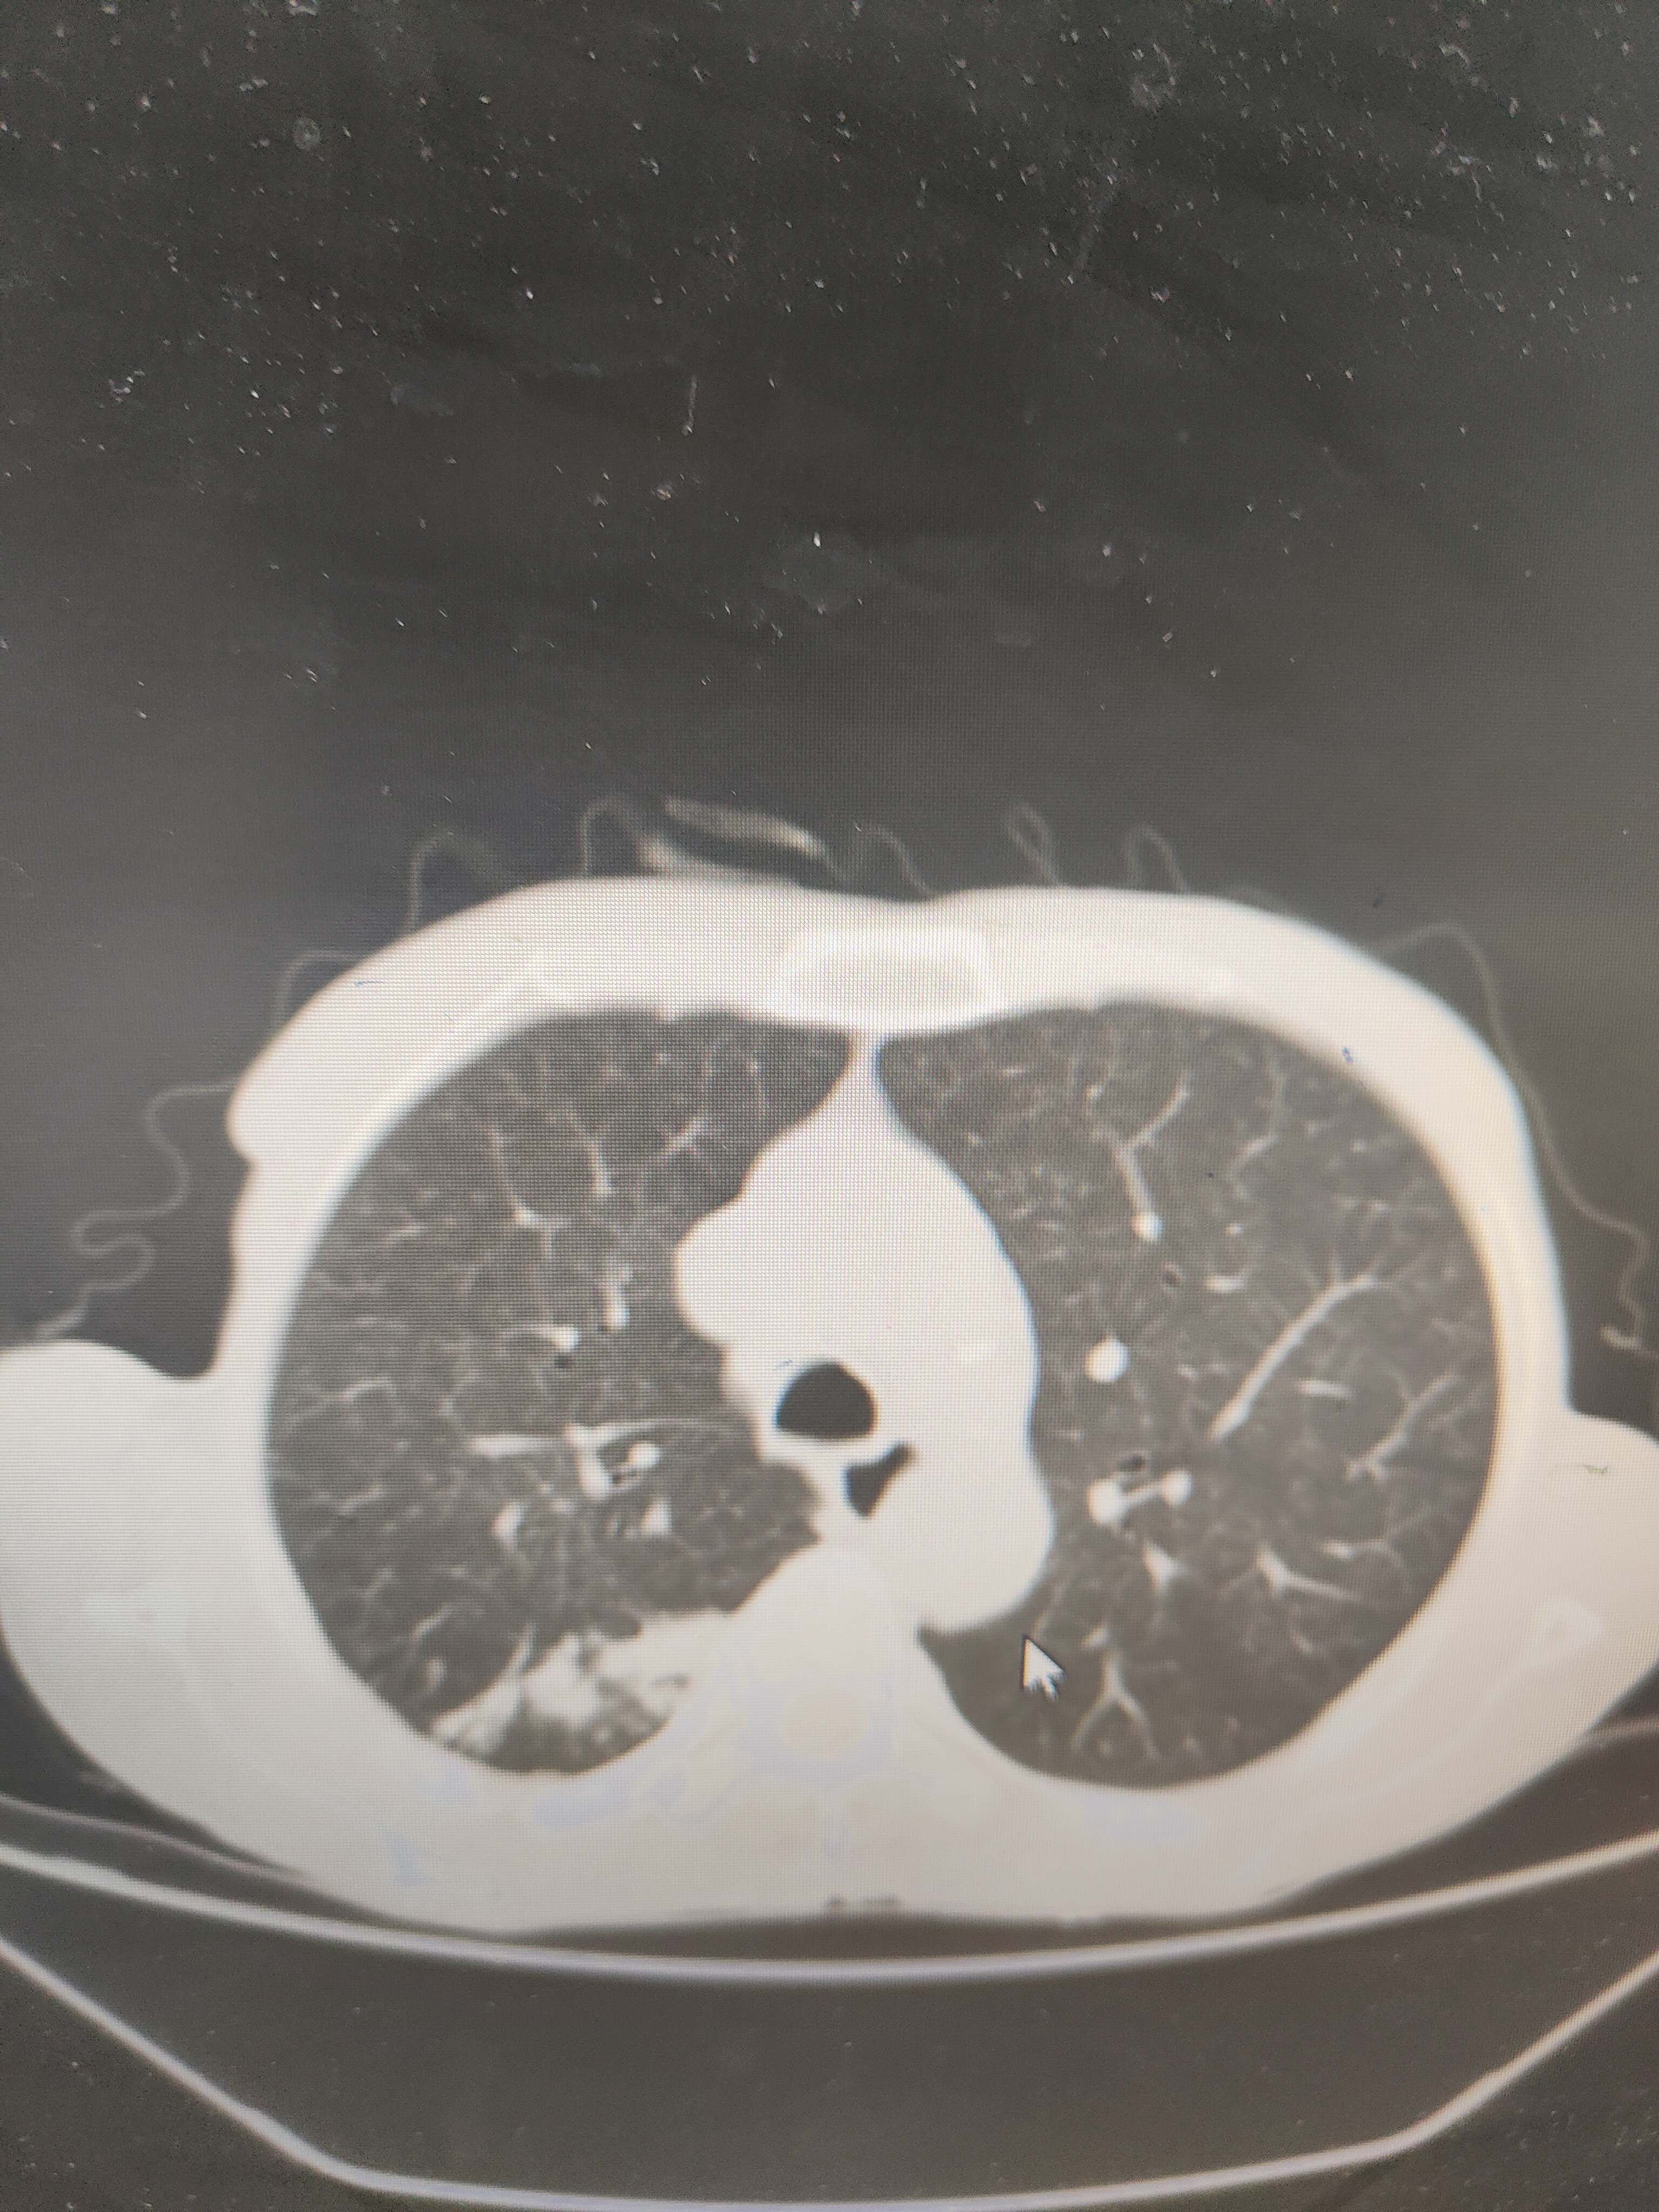

2021年5月首次肺部CT平扫,影像报告提示1.两肺慢性支气管炎、肺气肿、多发肺大疱;2.右肺中下叶多发感染性病变、结节、右肺门增大,建议治疗后复查或进一步检查排查右肺门区肿瘤性病变;3.左肺上段舌叶散在炎性病变

2021年8月因2型糖尿病入院复查肺部CT平扫,影像报告提示:胸部CT复查:1.右肺中下叶感染范围较前相仿、密度增高;2.右肺门区病变较前有所增大;3.右肺外基底段结节较前吸收。

2023年8月肺部CT平扫影像结果提示:1.右肺上叶密度增高影较前显著增大,建议进一步检查;2.两肺多发斑片结节灶较前增多,部分增大。

肺部增强CT影像学提示:右肺内大片不规则影轻度强化,肿瘤可能。